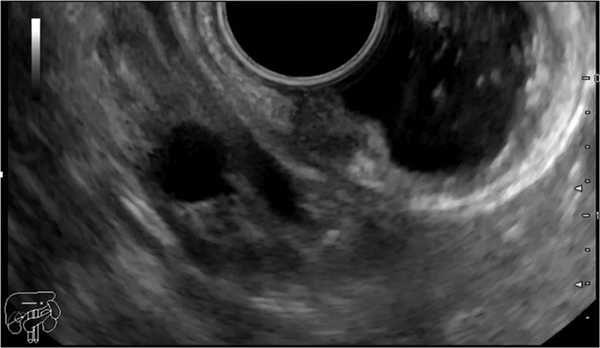

В ноябре 2019 г. пациент выполнил ЭУС (07.11.19), выявлено подслизистое образование нисходящей ветви ДПК (нейроэндокринная опухоль?). Проведено сканирование выявленного подслизистого образования нисходящей ветви ДПК (рис. 2): образование однородное, гипоэхогенное, исходит из 2-го эхослоя (глубокие слои СО). Размер 7´5 мм. Контуры размытые, неровные. Подслизистый слой под образованием прослеживается, выраженно истончен. Мышечный слой интактен. При эластографии обнаружено образование повышенной плотности. Парагастрально в области 4-й эхогруппы — множественные лимфатические узлы диаметром до 6 мм, округлые. По ходу печеночно-двенадцатиперстной связки — лимфатические узлы до 12 мм, с сохраненной кортико-медуллярной структурой. Заключение: ЭУС-картина, более вероятно соответствует НЭО нисходящей ветви ДПК, T1N0MX. Парагастральная лимфаденопатия. Лимфаденопатия по ходу печеночно-двенадцатиперстной связки.

Рис. 2. Подслизистое образование нисходящей ветви двенадцатиперстной кишки.